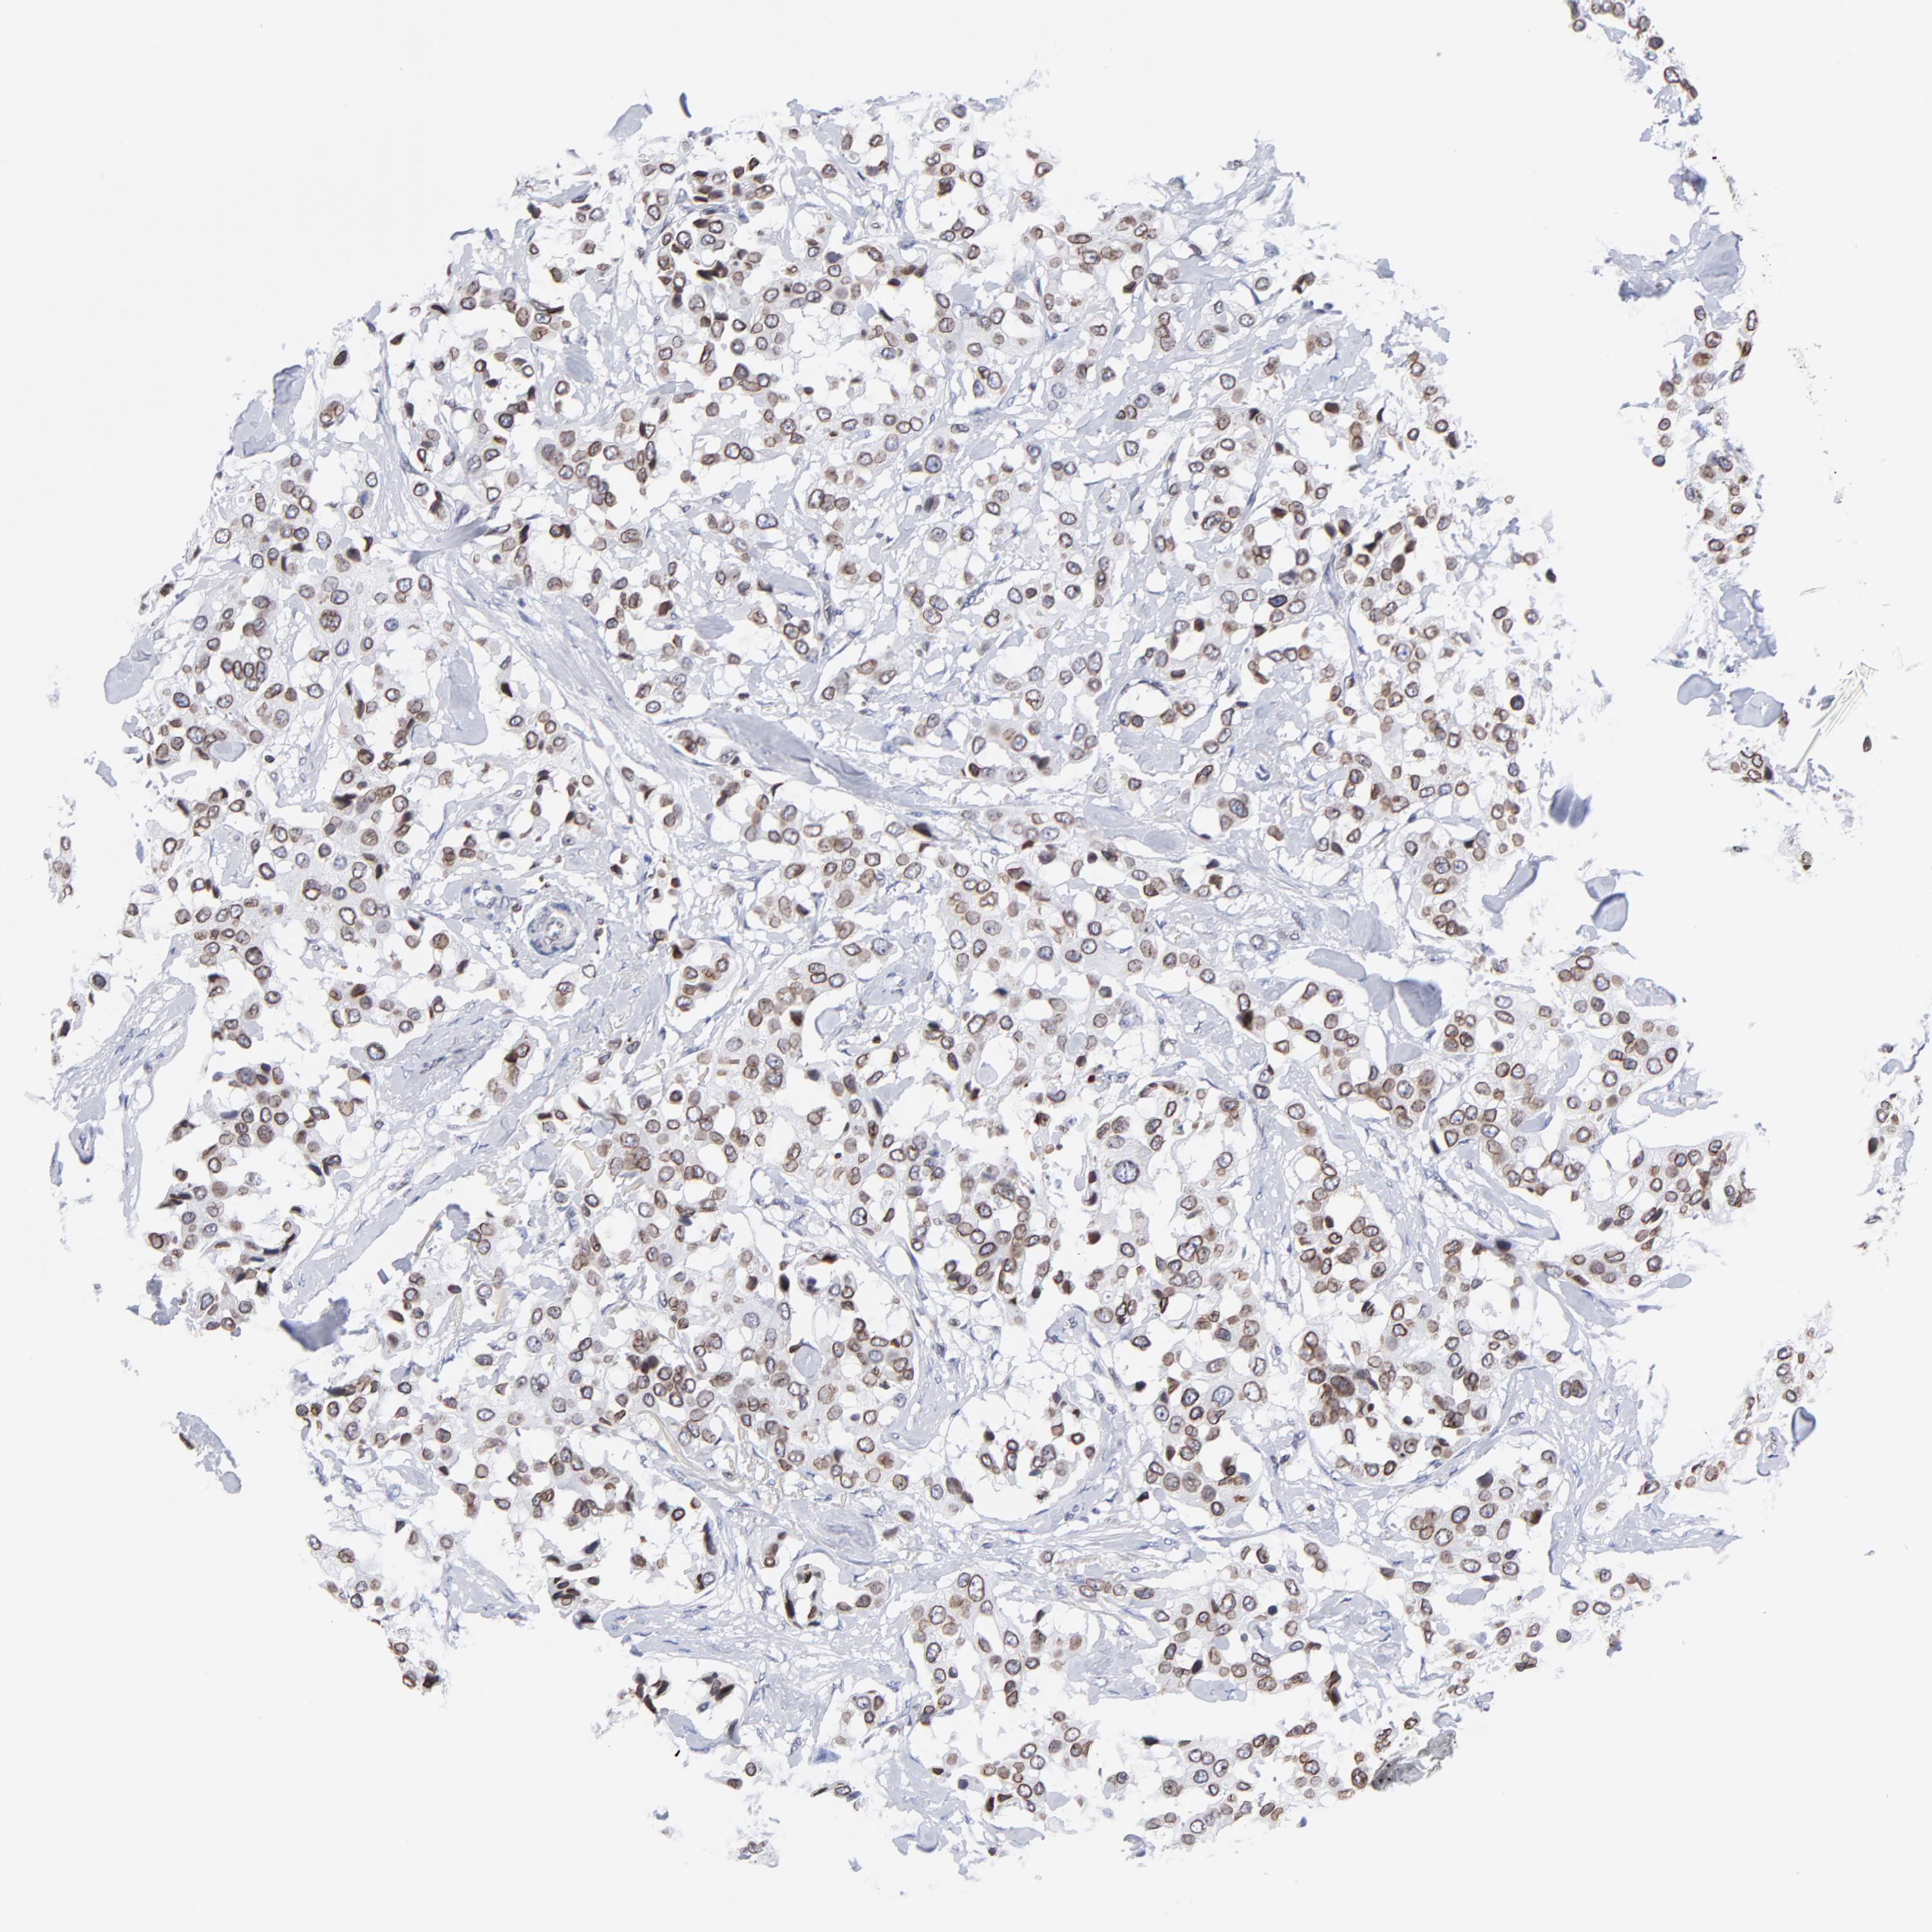

CANCER BREAST CANCER Show tissue menu

BRCA TCGA BRCA VALIDATION PROTEIN EXPRESSION

Breast cancer

Human cancer

THAP7 is not prognostic in Breast Invasive Carcinoma (TCGA)